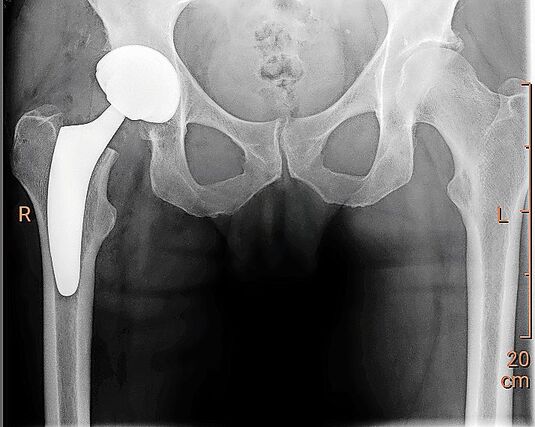

Die Prothese, also ein künstliches Gelenk, sollte immer die letzte Variante einer Behandlungsoption sein. Vorher sollten Therapiemöglichkeiten wie aktive und regenerative Bewegung mit Schwimmen und Velofahren oder andere mit der Physiotherapie erarbeitete Massnahmen in Betracht gezogen werden. Sind anhand eines MRIs bereits grössere Schäden im Gelenk erkennbar, können zum Teil mit einer Kniespiegelung degenerative Komponenten wie beispielsweise kleine lose Knorpelpartikel entfernt oder auch Meniskusrisse behandelt werden. Dadurch wird die Reizung der Gelenke meist deutlich reduziert. Wird diese Massnahme mit aktiver Bewegung kombiniert, kann eine Prothese teils noch länger hinausgezögert werden. Etwas Zeit gewinnen kann man auch durch Spritzen mit Kortison, Hyaluron oder Eigenblut, die direkt in das schmerzende Gelenk verabreicht werden.

Komplikationen sind heute zum Glück selten. Die Qualität der Gelenkchirurgie und auch die der Gelenkimplantate ist mittlerweile sehr hoch. Die Kunststoffmaterialien der Implantate nutzen sich kaum noch ab. Was eher vorkommt, sind Lockerungen der Implantate infolge von Stürzen, fortgeschrittener Osteoporose oder Infekten.

Wichtig ist, dass sich Menschen mit Prothesen allgemein vor bakteriellen Infekten in Acht nehmen, denn diese können über die Blutbahnen in den Bereich der künstlichen Gelenke gelangen und dann dort zu Entzündungen und Infektionen führen. Für den Einbau einer Gelenkprothese kann man aus medizinischer Sicht kaum zu lange zuwarten. Man sollte spätestens dann zum Arzt gehen, wenn die Beschwerden so gross werden, dass man den Alltag nicht mehr problemlos meistern kann.

[IMG 2]